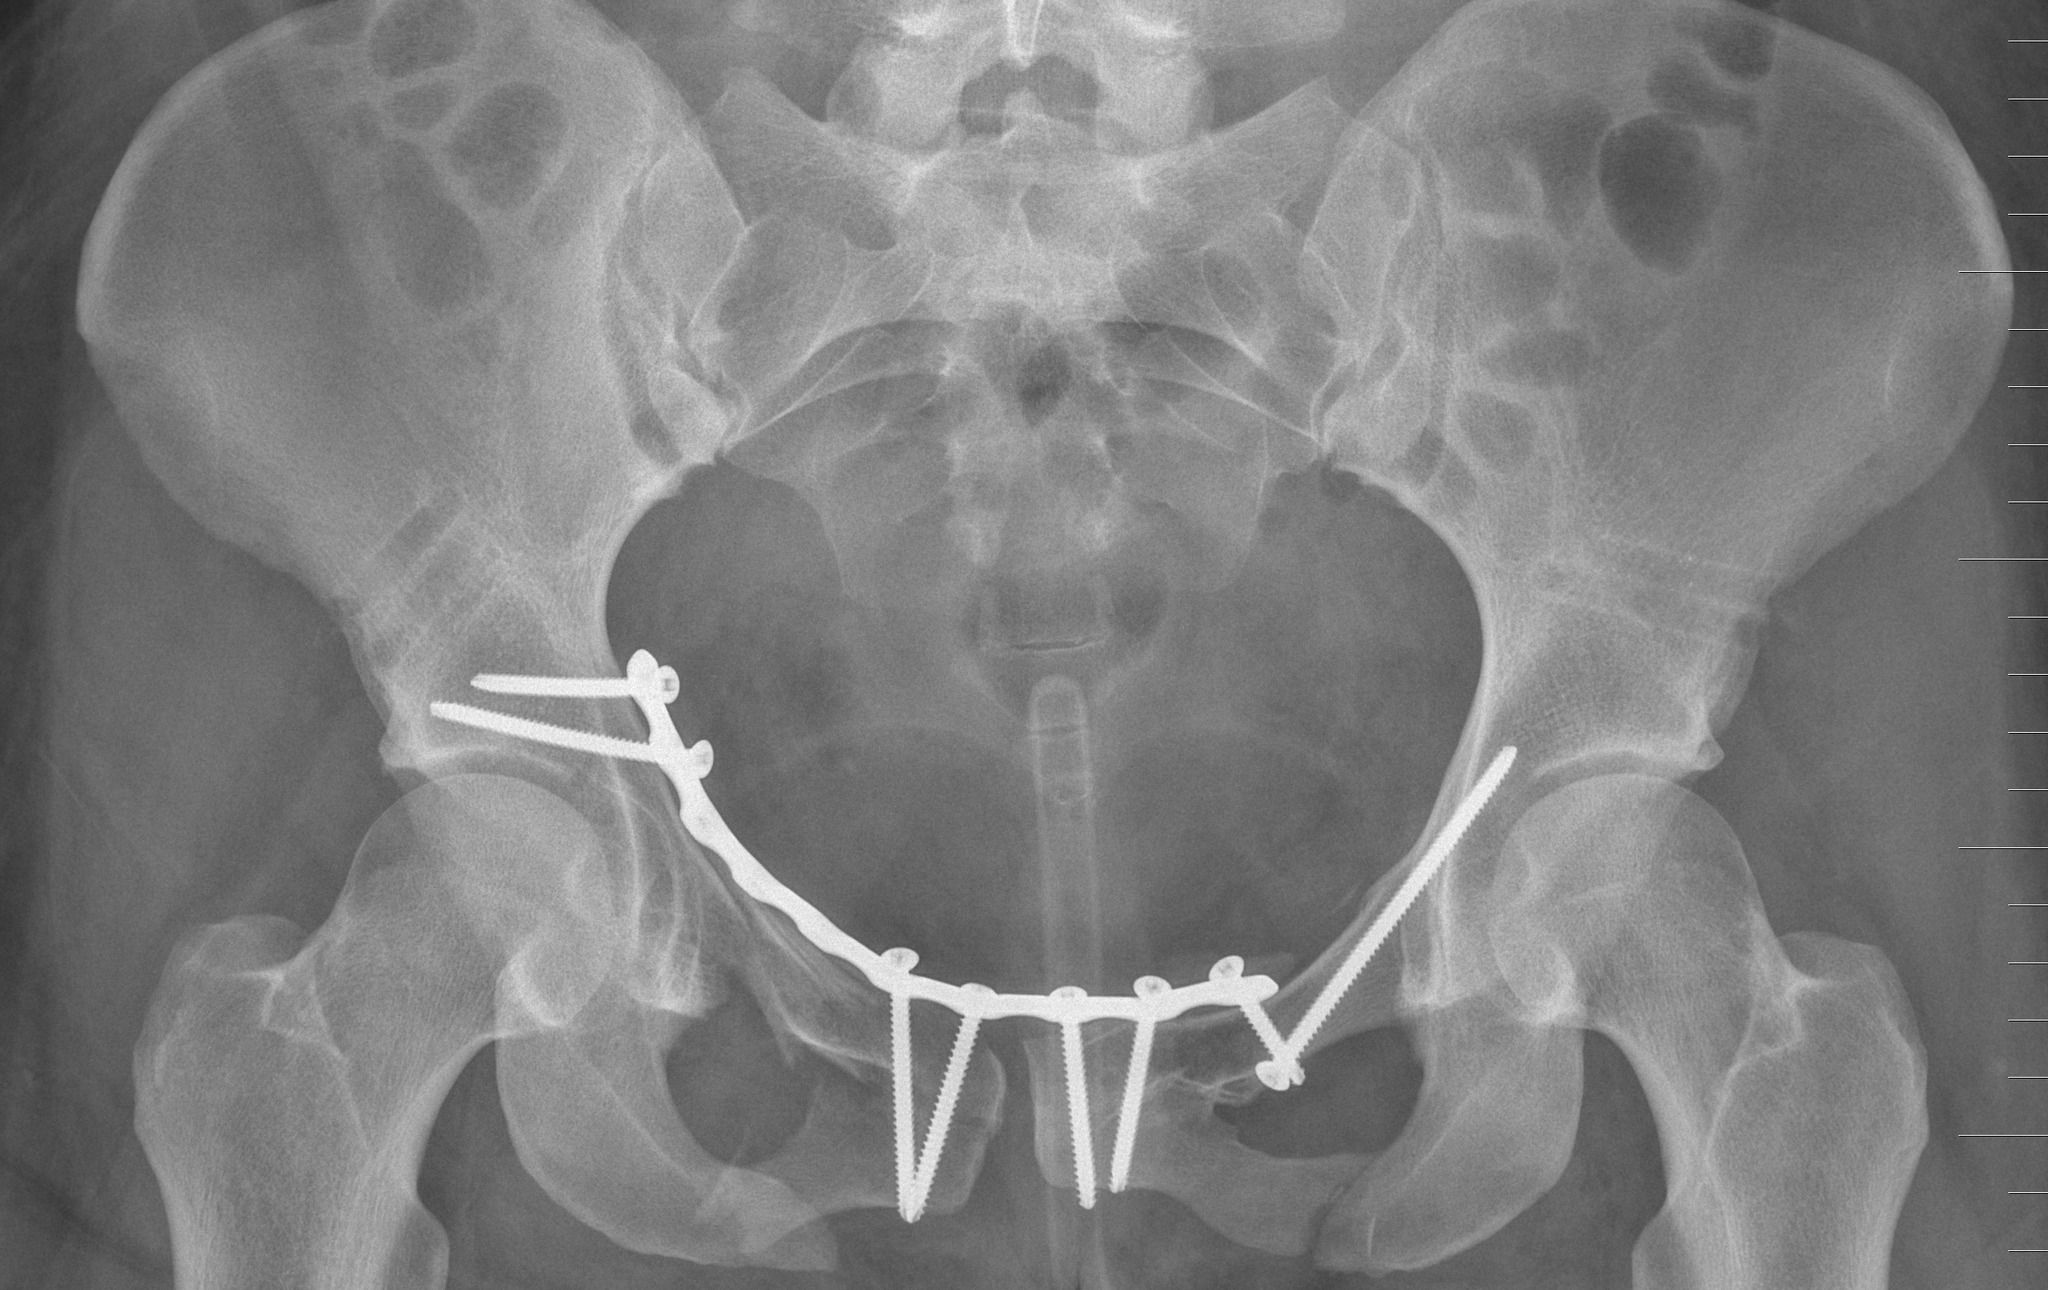

V piatok 9. júna 2023 absolvovala zranená motocyklistka mimoriadnu šesťhodinovú operáciu za účasti dvoch paralelných operačných tímov oddelenia úrazovej chirurgie FNsP Žilina. S ohľadom na rozsah a množstvo zlomením sa traumatológovia rozhodli pristúpiť k zložitému zákroku, počas ktorého vykonali otvorenú operáciu panvy a súčasne zlomenín na oboch horných končatinách. Ako uviedol primár žilinskej úrazovej chirurgie, špeciálny postup zvolili z dôvodu zníženia celkového času v anestézii. „Takéto výkony nie sú bežné, v sále sa nachádzalo takmer 15 ľudí, päť lekárov – operatérov, lekár a sestra z anestéziologického tímu, dva plné tímy inštrumentárok, rádiologická technička a ďalší zdravotnícki aj nezdravotnícki pracovníci,“ dodal J. Kacian. Pooperačný stav pacientky bol adekvátny rozsahu a závažnosti operačného výkonu, postupne sa však stabilizovali všetky životne dôležité orgány a následne bolo možné ženu previezť do neďalekej nemocnice bližšie k jej rodine a blízkym.